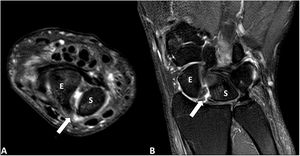

The case presented is that of a 30-year-old left-handed male who consulted for episodes of intermittent chronic pain in the dorsal aspect of the left wrist, which partially subsided after taking anti-inflammatory drugs. The condition began following an accidental fall from his height 2 years earlier, for which he did not consult. A posteroanterior wrist X-ray showed a scapholunate diastasis of 3.5 mm and a rotatory subluxation of the scaphoid (Fig. 1). The study was completed with ultrasound and magnetic resonance imaging (Figs. 2 and 3), which demonstrated a complete rupture of the dorsal component of the scapholunate ligament. The patient was referred to the Hand Unit for consultation, where surgical treatment with arthroscopic ligamentoplasty was decided.

Magnetic resonance imaging. Axial (A) and coronal (B) images of the left wrist in T2-weighted sequences with fat suppression (SPAIR). There is a complete rupture of the dorsal portion of the scapholunate ligament (arrow) producing a significant diastasis between the scaphoid bone (E) and the lunate (S) with minimal effusion and signs of synovitis. There are no foci of MRI signal similar to bone oedema suggestive of inflammation/arthritis or significant osteoarthritic changes.